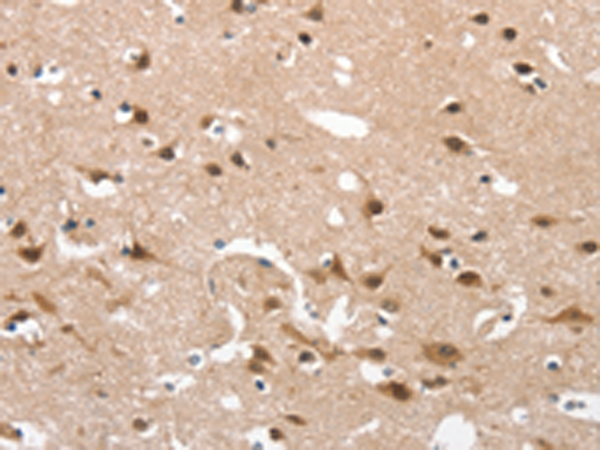

分类: 科研抗体货号: P04323别名: C17orf71应用: IHC反应种属: Human, Mouse